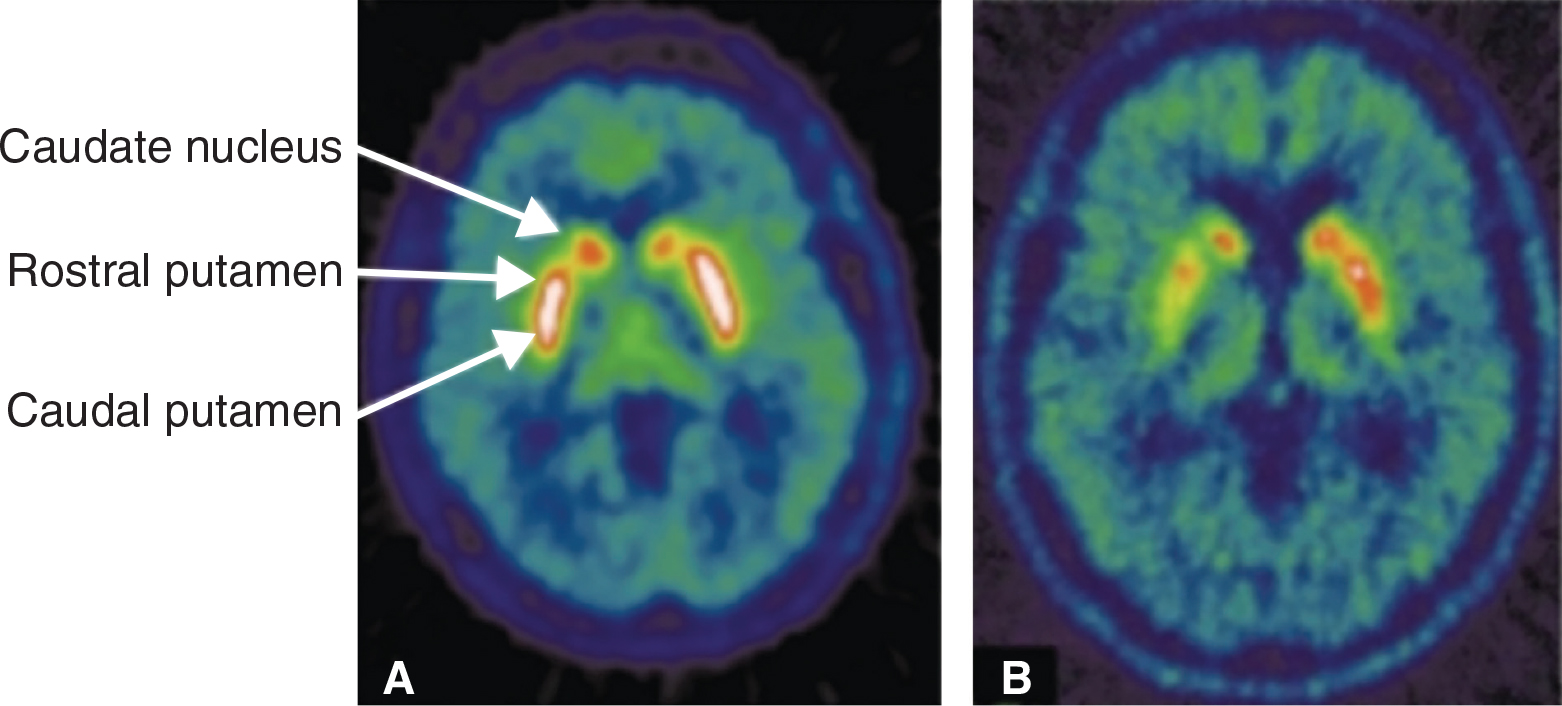

18F-fluoro-3,4-dihydroxyphenylalnine (F-DOPA) is a positron emission tomography (PET) agent that measures dopamine precursor uptake for the assessment of presynaptic dopaminergic integrity and has been shown to accurately reflect the monoaminergic disturbances in PD (31). F-DOPA brain imaging demonstrated a decrease in the caudate nucleus uptake in early stage of idiopathic PD with associated frontal lobe impairment such as attention suppression (32) (Figure 2). Several studies have shown high sensitivity and specificity of F-DOPA PET. For example, a study by Biju et al. reported sensitivity and specificity of 90%–100% and 91% respectively (33). Recently, Ibrahim et al. also reported sensitivity of 95.4% and specificity of 100% (34). There is a strong correlation between the findings on the F-DOPA PET scan in the putamen and the severity of the disease evaluated with the Unified Parkinson Disease Rating Scale (UPDRS) (35, 36) as well as bradykinesia and rigidity (37).

Fig 2

Figure 2. Transverse 18F-DOPA PET images. Healthy control (left) and patient with idiopathic PD (right). In PD, there is asymmetric loss of uptake of the tracer, and more pronounced loss in the caudal putamen than in the rostral putamen and the caudate nucleus.

Source: Am J Transl Res 2011;3(4):323-41. Published with permission.